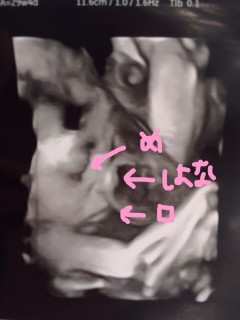

頭が少し大きめの直径7.7cm、体重が1458g順調で喜ばしいのだけど… 潰れて横に広がった鼻・分厚い唇がブサイクでとてもとてもショック。 女の子なのに人生ハードモードになるんじゃないか申し訳ない(涙) 先生が書いてくれたイラストがカワイイのがまた泣ける初めて書いてくれたけれど、赤ちゃんがあまりにブスで哀れに思ってくれたのだろうか あぁなんだか情緒不安定になる~! 2週間後は可愛く写ってくれますように。